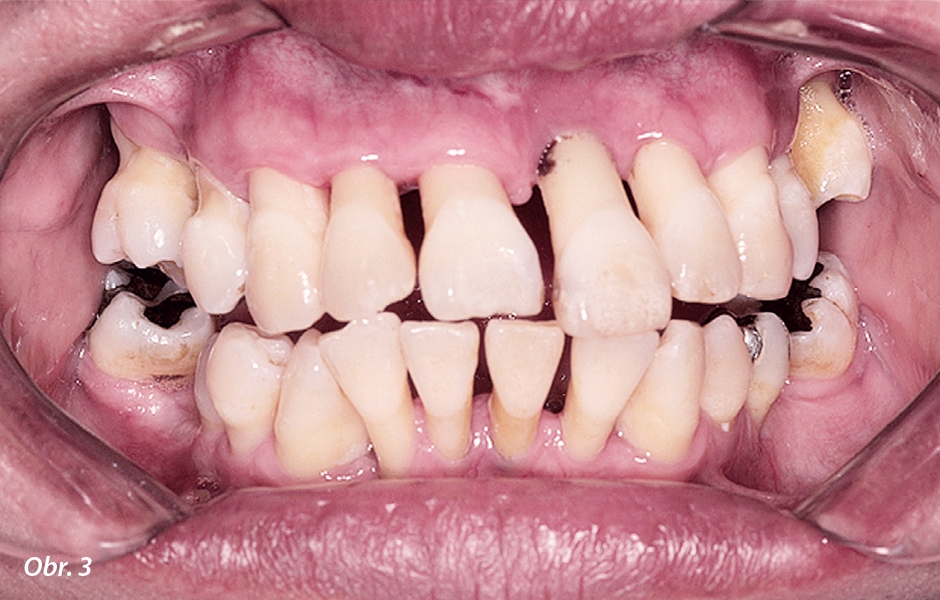

V selhávajícím chrupu horní i dolní čelisti byly přítomny viklavé a posunuté zuby, narušená okluze a ztráta kosti (obr. 3). Aby bylo možno určit nejvhodnější léčebné alternativy s ohledem na kvalitu a denzitu kosti a také přání pacienta, byla analyzována data z CBCT. Při využití pokročilého softwaru (Blue Sky Plan, Blue Sky Bio) mohou být díky všem potřebným pohledům (příčné, koronální, sagitální, axiální) a také díky 3D rekonstruovaným povrchovým modelům detailně vyhodnoceny diagnostické informace pro plánování implantologického zákroku. Lze tak určit vhodné oblasti pro implantáty a pomocí všech dříve zmíněných pohledů následně umístit virtuální implantáty.